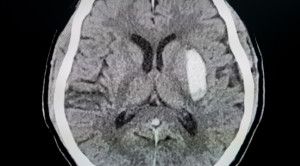

• Pilihan Pemeriksaan Radiologi untuk Stroke Hemoragik

Pilihan Pemeriksaan Radiologi untuk Stroke Hemoragik

Dalam menentukan diagnosis stroke hemoragik, pemeriksaan radiologi seperti CT scan kepala menjadi penting untuk mengidentifikasi lokasi dan tingkat keparahan perdarahan otak. Stroke...(Baca Selengkapnya)